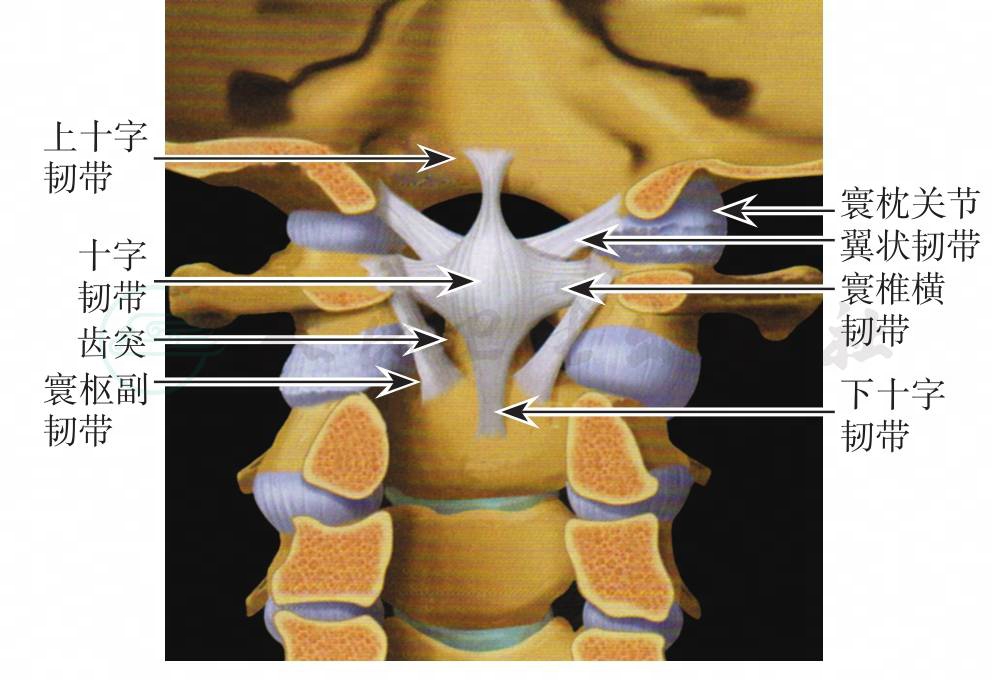

寰枕关节由枕骨髁与寰椎上关节面组成(图1),关节囊以及枕骨大孔与寰椎之间的寰枕前、后膜共同维持关节的稳定性。而枕骨与枢椎之间的覆膜、翼状韧带和齿突尖韧带等也参与维持其稳定性(图2,图3)。关节的过伸运动主要受覆膜的限制,过屈运动则受到颅骨与寰椎前缘的骨性接触限制。侧弯和旋转运动主要受翼状韧带的限制。寰枕关节的活动范围为:屈25°→←伸25°,左右侧屈以及一侧轴向旋转范围均为5°。由于寰枕关节紧邻脑干、脑神经及椎动脉,如骨折同时造成这些结构的损伤,可导致部分病例在得到救治之前死亡。但有些经过抢救幸存的患者中,经过治疗后甚至能够完全康复。该病在儿童的发生率大于成人,由于儿童的枕骨髁发育未完善,寰枕关节面较平坦且易脱位,其关节周围的韧带较为松弛,因此其关节的稳定性较差。

图2 枕颈部关节韧带